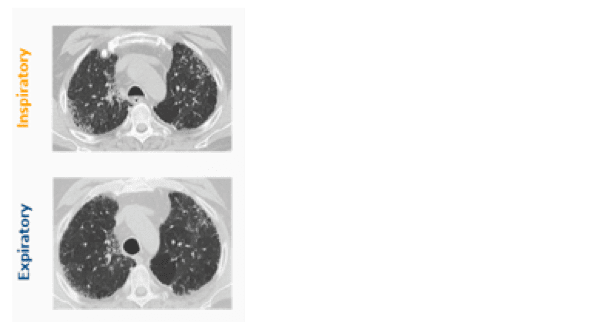

Een HRCT-scan bevestigt dat Robert longfibrose heeft:

• mozaïekpatroon zichtbaar op inspiratoire beelden; bevestiging van air trapping op expiratoire beelden

• reticulaties perifeer; geen ‘honeycombing’

• matglas (niet bevestigd)

• betrokkenheid bovenste en onderste longvelden